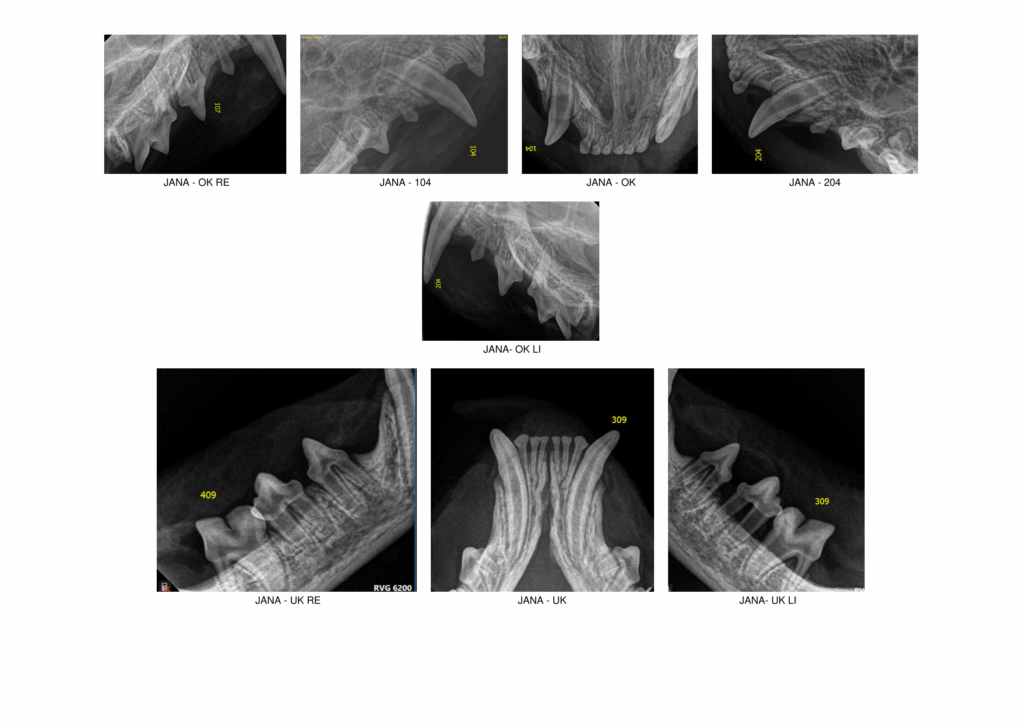

Report example: